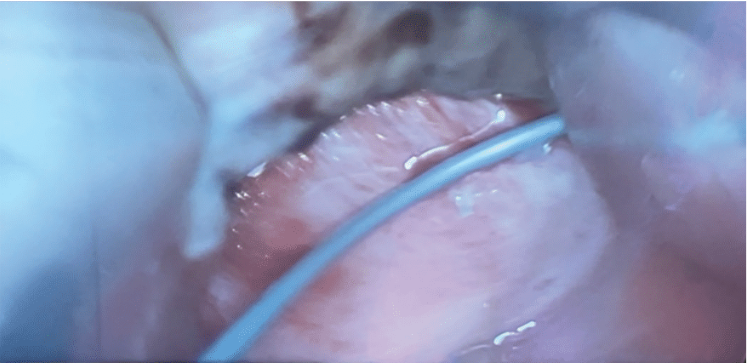

The hybrid Convergent procedure is performed as a staged approach. The cardiac surgeon performs epicardial PV and LA posterior wall ablation

and epicardial LA appendage (LAA) closure; then, 45 days later, the electrophysiologist performs endocardial LA ablation to address gaps and additional LA substrate along with a right-sided cavotricuspid isthmus (CTI) ablation, if needed. Prior to procedure, the patient underwent intraoperative transesophageal echocardiogram (TEE) to evaluate for the presence of thrombus in the LA. During the surgical portion of the procedure, an endoscopic subxiphoid approach was used through the pericardial space and a 23-lesion set was completed, some of which were double applications utilizing the EPi-Sense system (AtriCure, Inc) (Figure 1). During ablation, some anatomical difficulties were noted due to the prominence of the patient’s spine and oblique sinus reflections. After completion of the epicardial ablation, the LAA was excluded with the AtriClip (AtriCure, Inc) via a thoracoscopic approach. At the end of the surgical portion of the procedure, the patient was successfully cardioverted to sinus bradycardia. The patient did well postoperatively, all drains and chest tubes were removed, and he was discharged home in sinus rhythm on postoperative day 2. There were no complications from the surgical portion of the procedure.